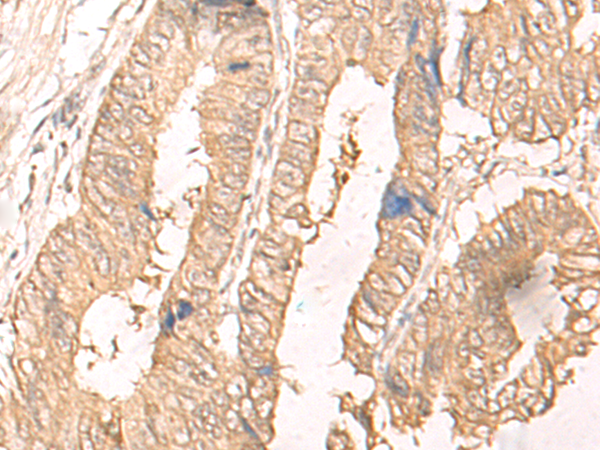

IHC positive control: |

Human cervical cancer and Human colorectal cancer |